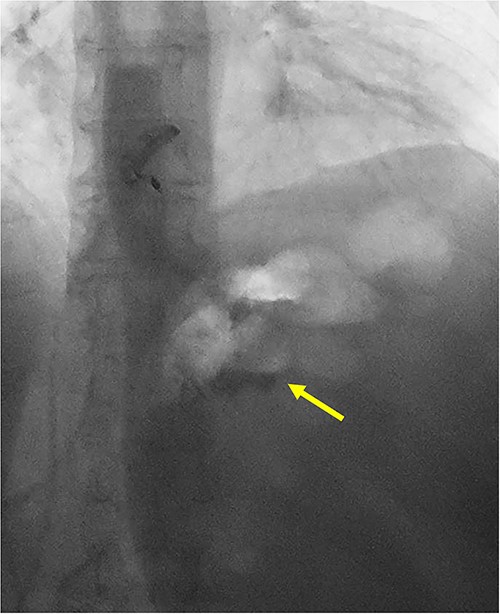

An intra-operative EGD was performed to assist with localizing the GGF and demonstrated a wide-mouthed fistula ~2 cm proximal to a widely patent GJ without an associated marginal ulcer. Purple cartridges on the Signia staple gun were then used to divide the remnant stomach at the level of the mid-body as well as the lateral aspect of the gastric pouch. Extreme care was taken to ensure the GJ and roux limb were preserved and not injured during this step. The en-bloc GGF specimen was removed and inspected on the back table demonstrating the fistulous connection between the remnant stomach and gastric pouch, ensuring a complete resection of the fistula (Figs 4 and 5). The total operative time was 1 h and 21 min.

En-bloc resection of gastrogastric fistula with excised portions of gastric pouch (arrow) and gastric remnant (asterisks).

Scissors placed through gastrogastric fistula demonstrating complete resection of fistula.